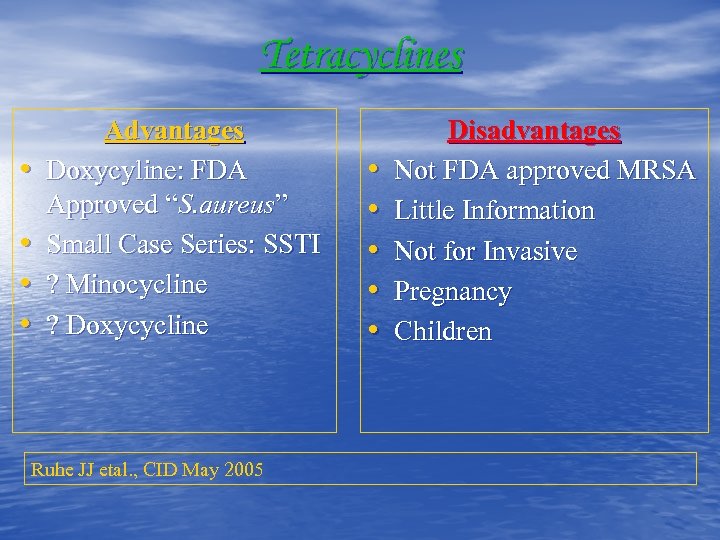

Tetracyclines • • Advantages Doxycyline: FDA Approved “S. aureus” Small Case Series: SSTI ? Minocycline ? Doxycycline Ruhe JJ etal. , CID May 2005 • • • Disadvantages Not FDA approved MRSA Little Information Not for Invasive Pregnancy Children

Tetracyclines • • Advantages Doxycyline: FDA Approved “S. aureus” Small Case Series: SSTI ? Minocycline ? Doxycycline Ruhe JJ etal. , CID May 2005 • • • Disadvantages Not FDA approved MRSA Little Information Not for Invasive Pregnancy Children